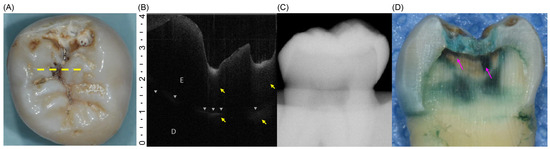

Optical Coherence Tomography for Assessing the Severity of Dental Caries: An In Vitro Validation Study

by In-Kyung Hwang, Sun-Young Kim and Tae-Il Kim

Background/Objectives: Differentiating initial from moderate non-cavitated occlusal caries using intraoral radiography is challenging. This in vitro study aimed to verify the ability of Optical Coherence Tomography (OCT) to discern the extent of demineralization in non-cavitated carious lesions and discriminate between the exact [...] Read more.

Background/Objectives: Differentiating initial from moderate non-cavitated occlusal caries using intraoral radiography is challenging. This in vitro study aimed to verify the ability of Optical Coherence Tomography (OCT) to discern the extent of demineralization in non-cavitated carious lesions and discriminate between the exact caries stages. Methods: In total, 110 extracted molars and premolars with occlusal caries were examined by two calibrated examiners using OCT and radiography. Histological sections stained with acid red were used as the reference standard. Diagnostic accuracy was calculated by comparing OCT- and radiograph-based diagnoses with the histologic reference standard. Results: OCT demonstrated superior sensitivity (0.83), specificity (0.76), and overall diagnostic accuracy (0.79) for distinguishing moderate from initial lesions, outperforming intraoral radiography, which achieved a sensitivity of 0.48, specificity of 0.84, and accuracy of 0.70. McNemar’s test showed a significant difference in sensitivity (p < 0.05), but not in specificity (p > 0.05), between the two diagnostic methods. Conclusions: These findings confirm that OCT can visualize caries progression with sufficient precision to distinguish between the initial and moderate lesion stages in an in vitro setting. Further validation in clinical trials is necessary to support OCT’s application for routine caries diagnosis. Full article